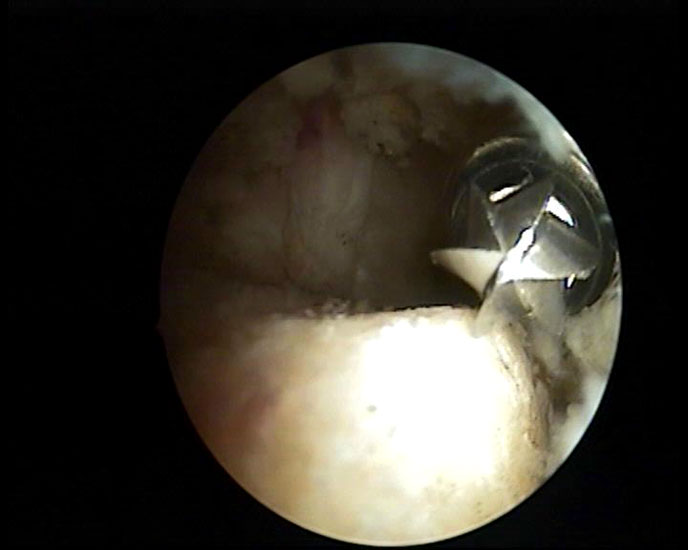

Abbildung 8, Video 3

Nach vollständiger Darstellung erfolgt die Resektion der Exostose mit einem Acromionizer von medial, wobei auch hier die geschlossene Seite des Arbeitsansatzes zum Schutz der Achillessehne nach dorsal ausgerichtet werden sollte. Verwendet werden können wahlweise Kugel-, Zapfen- oder Walzenansätze mit 3,5-5,5 mm Durchmesser. Ein kleinerer Durchmesser vereinfacht zwar das Handling im engen retrocalcanearen Raum, erfordert aber einen höheren zeitlichen Aufwand als die Verwendung einer höherkalibrigen Fräse. Der Knochenabrieb verstopft dünne Instrumente häufig und der Durchfluss der Spülflüssigkeit ist gering. Es hat sich bewährt, zwei verschiedene Größen bereitzuhalten und ggf. intraoperativ zu wechseln.